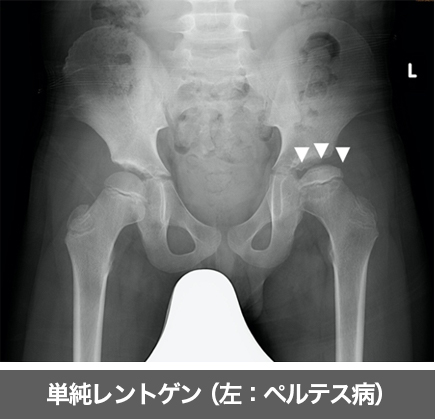

大腿骨頭の骨成熟過程で血行障害により骨頭が壊死してしまう病気です。5歳から7歳の男児に多く、発症年齢や病期、病態により治療方針を選択します。壊死部の修復には数年を要します。

ペルテス病に対しては、坐骨免荷装具等による保存療法と手術治療(骨切り術)があります。